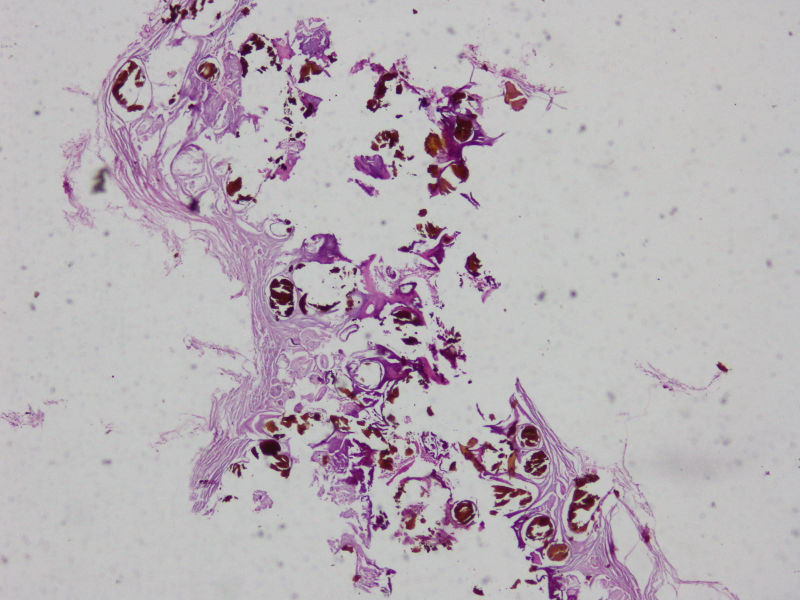

网膜结节

图1